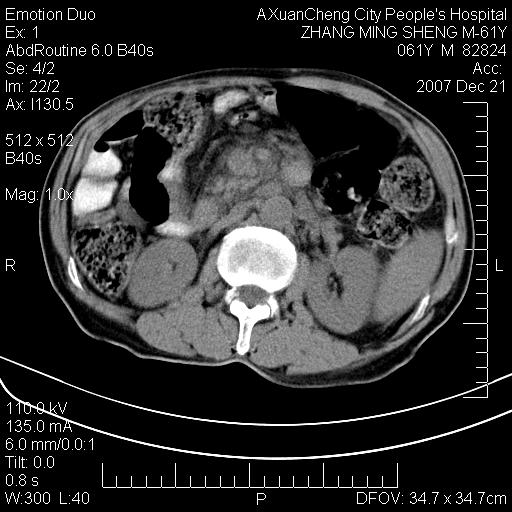

标题: CT11031:M61Y,胰腺占位 [打印本页]

标题: CT11031:M61Y,胰腺占位

大家侃侃门静脉和胆管系统怎么回事,肝内转移?

1,肝硬化,脾大.

2,肝内多发结节状低密度占位,伴门脉及肠系膜上v栓子形成.考虑a;门脉及肠系膜上v血栓后肝改变.b;弥漫型肝癌伴门脉及肠系膜癌栓.

肝硬化,门脉高压,脾肿大;弥漫性肝癌,肝内、门脉、腹膜后淋巴结转移,肝内外胆管扩张,胰头区占位,建议mr检查

胰腺癌伴肝内转移;门脉、肠系膜上v癌栓形成。

考虑为:胰腺癌伴肝脏转移、腹膜后淋巴结转移,门静脉及肠系膜上静脉瘤栓形成。

胰体尾癌伴肝内转移,门静脉及肠系膜上静脉瘤栓形成.